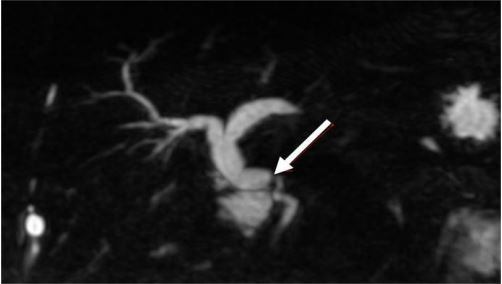

Paciente foi submetido a transplante hepático em outubro de 2016. Teve boa evolução no pós-operatório, com seguimento ambulatorial regular. Outros antecedentes: Infarto Agudo do Miocárdio há 4 meses e Doença Pulmonar Obstrutiva Crônica. Dois anos pós-transplante, paciente retorna com prurido progressivo, colúria, acolia fecal e icterícia há 15 dias. Traz consigo exames recentes: Hb= 10,5g/dl; Leucócitos= 8.500mm³ ; Plaquetas= 145.000mm³ ; Bilirrubinas total= 10,9mg/dL; Albumina= 4,5gdL; Fosfatase alcalina= 365U/L; Gamaglutamiltransferase= 1320U/L; AST= 34U/L; ALT= 24U/L; RNI=1,12; Creatinina= 0,8mg/dL. Ultrassonografia Doppler de abdome com achado de perviedade de vasos em hilo hepático e dilatação de árvore biliar intra-hepática. Solicitado colangiorressonância com imagem abaixo: